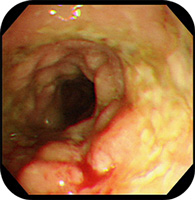

肉芽腫性外陰炎の1例臨床皮膚科 66巻2号医書.jp。